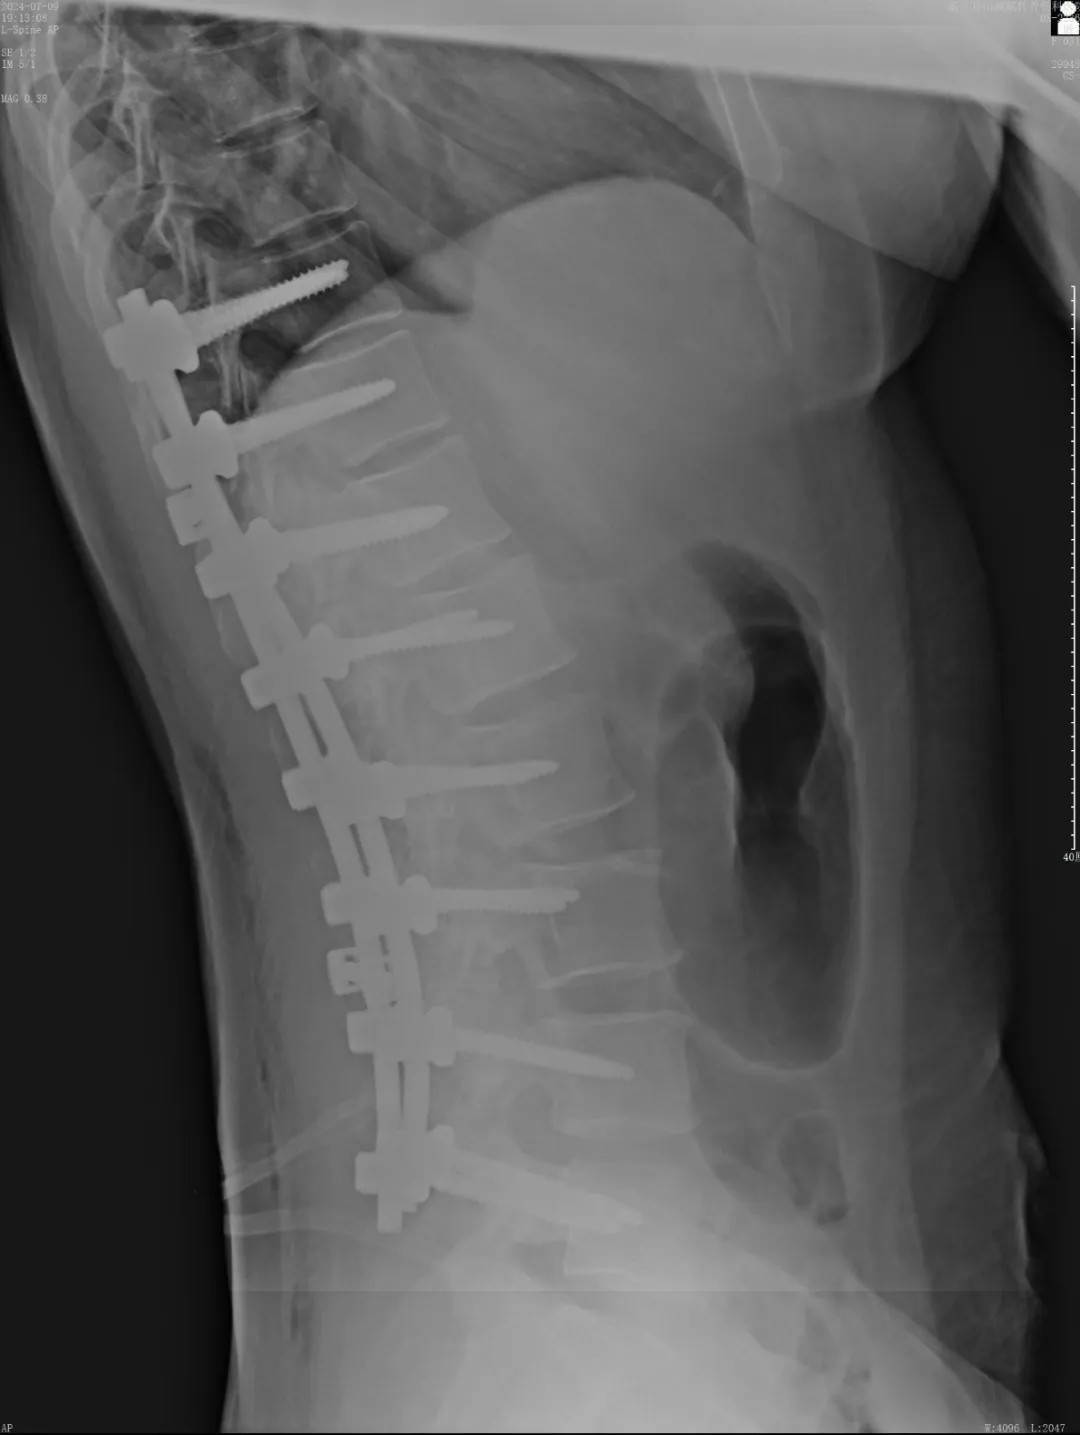

近日,文女士(化名)來院復(fù)診,整體恢復(fù)良好,術(shù)前活動(dòng)不便的癥狀明顯好多了,腰背部肌肉也恢復(fù)了一些,脊柱生理曲度相比術(shù)前有所恢復(fù),側(cè)彎癥狀也明顯改善,下胸椎、腰椎向左側(cè)側(cè)凸畸形較前改善,腰背部轉(zhuǎn)側(cè)活動(dòng)不利較前改善。